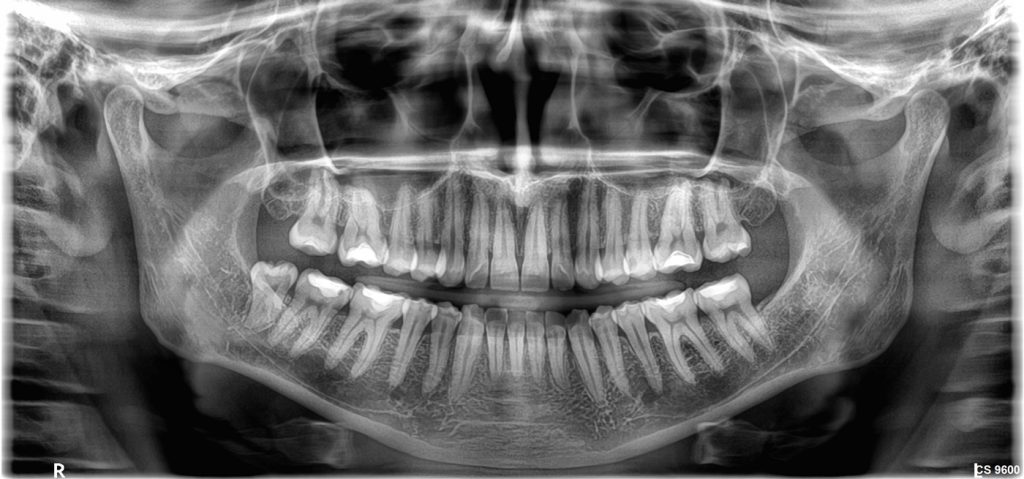

- Άριστη ψηφιακή Πανοραμική ακτινογραφία (2D).